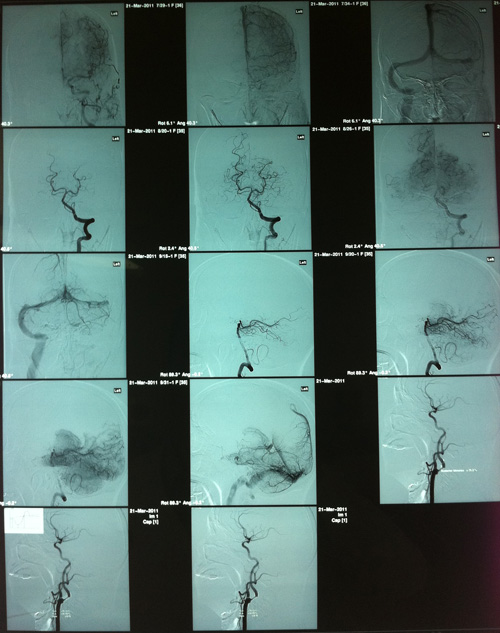

DSA(2011-3-21,人民医院):双侧颈内动脉起始部及右颈内动脉虹吸段及右侧大脑后、小脑上动脉起始段多发动脉硬化斑块形成,伴不同程度的管腔狭窄。